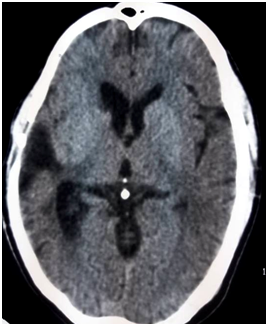

After hospitalization, an urgent CT scan of brain did, which revealed massive hematoma occupying the right sylvian fissure and adjacent parietal lobe (Figure 1). MRI of brain showed T1WI heterogeneously hyper intense lesion present within the right sylvian cistern and adjacent temporo-parietal area. The lesion had multiple intrinsic flow voids in T2WI (Figure 2). Due to initial presentation as intracranial hemorrhage and presence of multiple flow voids in T2WI, a CT angiogram of cerebral vessels was done to sort out the pattern of vascular pathology. CT angiogram showed a saccular aneurysm at the bifurcation zone of right MCA (Figure 3A). After successful clipping of the aneurysm, repeat CT angiogram with 3D reconstruction sequence revealed AVM, supplied by angular artery of right MCA (Figure 3B).

Figure 1 CT scan of brain, axial section showing massive hemorrhage at the right parietal lobe with compression in the lateral ventricle and midline shifting.